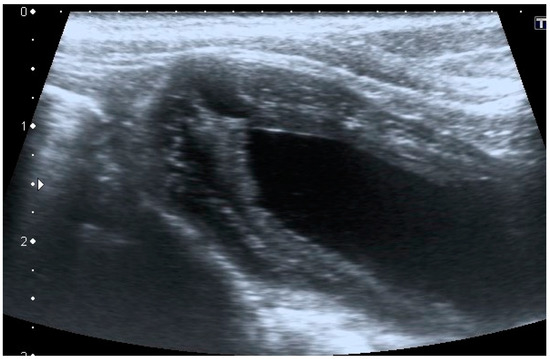

Urachal cyst: only five patients (two cats and three dogs) had this UA. Urachal cysts appeared as round structures in continuity with the bladder wall, with thin and hyperechoic walls and regular margins. It was of different size, from 0.2 to 0.5 cm and the content was always anechoic (Figure 4).

Figure 4. Longitudinal ultrasound image of the cranioventral part of the urinary bladder in a cat, showing the presence of a small (<1 cm diameter), well-defined, round, thin-walled, anechoic formation, cranial to the bladder apex, consistent with urachal cyst. The urinary bladder is empty.